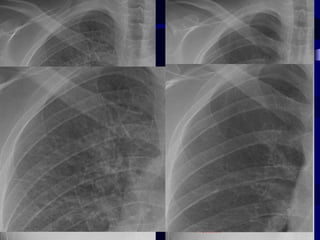

Retro sternal space   Retro cardiac space

1 1: Adequate penetration of 4 a the mediastinum-is the a thoracic spine seen? 2: Has the patient taken a good inspiratory effort? About 8-10 7 posterior thoracic ribs should be seen through the lungs 3: Is there any rotation of the chest? Assessed by checking 10 the upper thoracic spinous process (oval) in relation to the medial ends of the clavicles (lines ‘a’) - this CXR is rotated to left